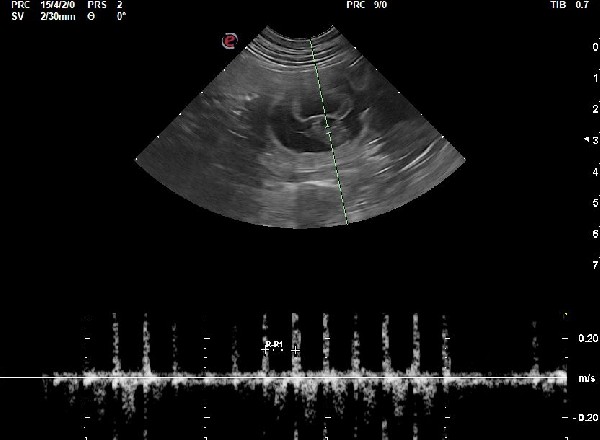

En plus de confirmer la gestation, elle permet de contrôler l’aspect des ampoules, des placentas, des ovaires et de l’utérus. Elle permet aussi d’estimer avec une bonne précision le nombre de chiots si elle est faite au moment optimal (autour de J25 post-ovulation). Si la date d’ovulation n’est pas connue, l’échographie peut permettre de dater la gestation grâce à différentes mesures anatomiques et à l’évolution des structures anatomiques visibles à l’échographie. Elle permet également de mettre en évidence et de suivre d’éventuelles résorptions embryonnaires et nous amène alors à réaliser d’autres examens.

Dans certains cas de figure, notamment lors d'antécédents d'avortement, un suivi de la progestéronémie peut être recommandé au cours de la gestation et peut être associé à des contrôles échographiques.